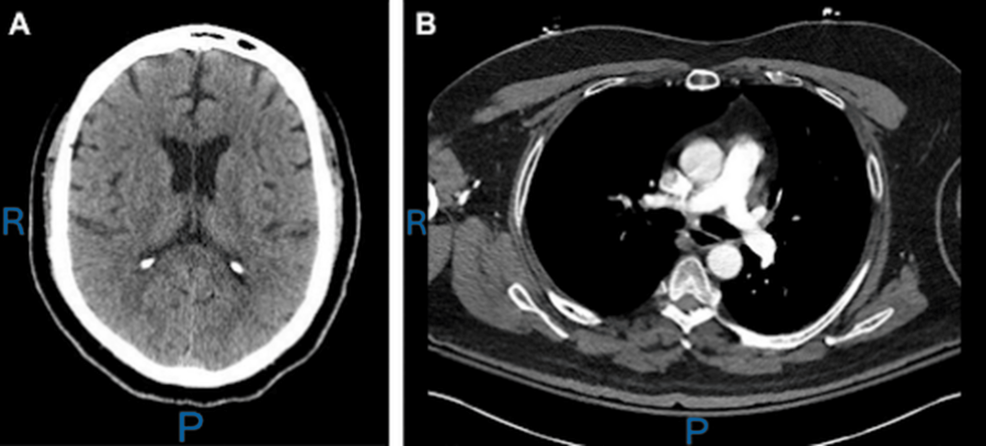

Un reporte de caso publicado por Cureus describe un escenario clínico donde la toxicidad por bupropión se manifestó con síntomas similares a los del síndrome de abstinencia alcohólica.